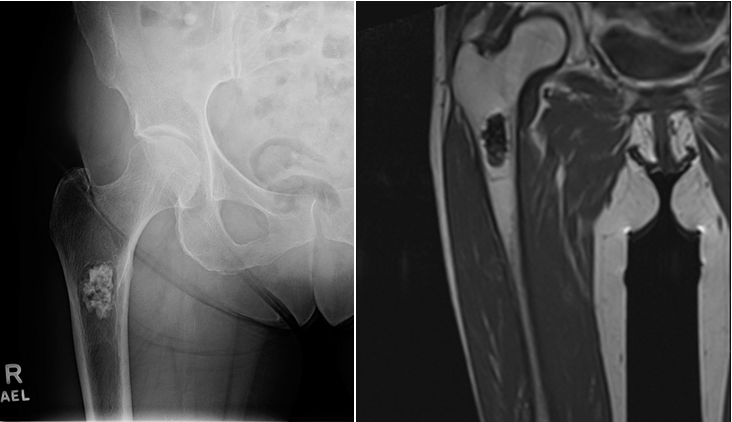

A 79-year old female presents with complaints of right hip pain for 2 months. She denies prior injury or precipitating event. The pain is made worse by lying on the affected side and occasionally hurts with hip motion. The pain is improved with NSAIDS and placing ice on the lateral aspect of her hip. Her primary care physician ordered x-rays which showed a bone lesion in the proximal femur. Her PCP was concerned she had bone cancer and ordered an MRI of the thigh to further evaluate. AP x-ray and a coronal MRI image are shown above. The patient denies a history of weight loss, fatigue, and history of cancer. On exam the patient has no pain with passive range of motion of the hip in all planes. She has pain with palpation over the greater trochanteric bursae. Motor and sensation are intact throughout the lower extremities. What is the most likely cause of this patient’s pain?